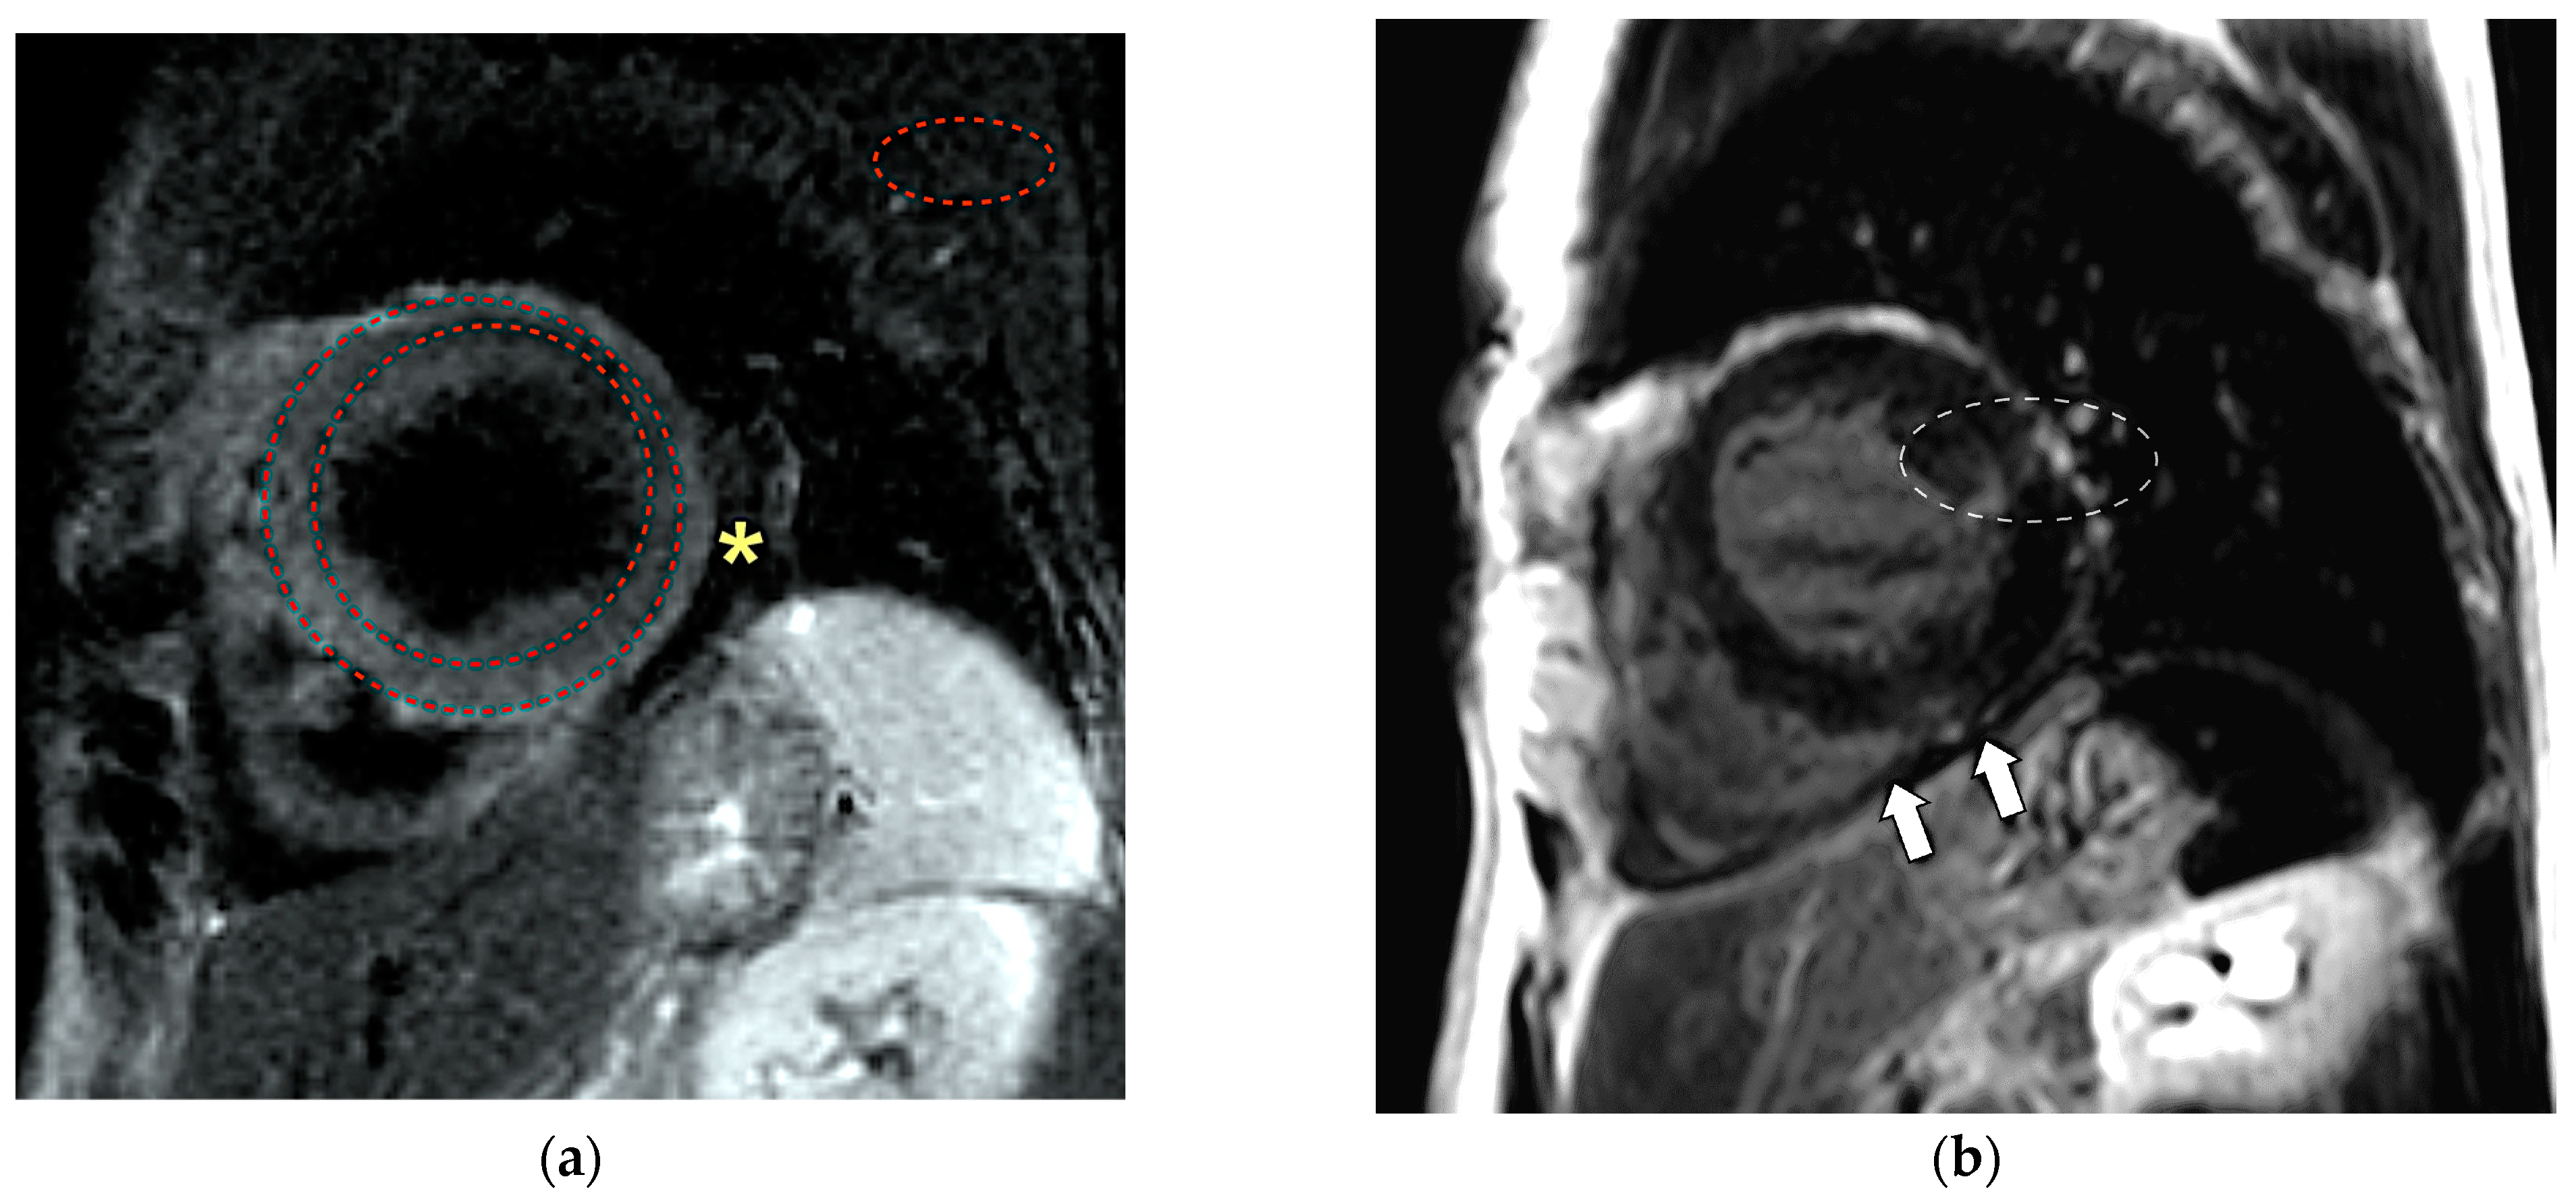

3. Case Presentation